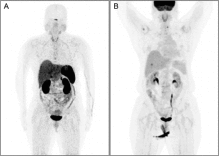

为了尽快控制病情,张阿姨接受了完全切除术,然而不幸的是,手术后不久就出现了转移,并且由于她的生长抑素受体表达极低,生长抑素类似物和肽受体放射性核素治疗等常规手段均无法应用,只能不断尝试各类化疗药物。让医生束手无策的是,在使用了包括卡铂、依托泊苷、卡培他滨、替莫唑胺、紫杉醇在内的多种化疗药物,以及依维莫司和阿特珠单抗等治疗方案后,肿瘤仍在疯狂增长,张阿姨病情持续恶化,出现无数皮下结节、左侧胸膜转移、多发性骨转移和脑转移等严重状况...

奇迹就这样发生了,治疗仅1个月迅速起效,张阿姨所有转移性肺病灶实现完全缓解。更令人欣喜的是,从开始接受恩曲替尼治疗至今,已持续获益至少一年,目前治疗仍在顺利进行中。